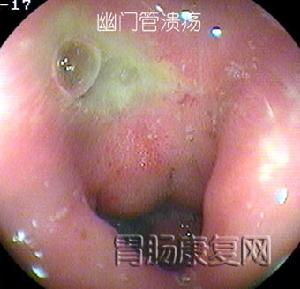

4.容易漏診:幽門管潰瘍行X線鋇餐檢查容易漏診,故走張行胃鏡檢查。胃鏡下可直接觀察到潰瘍的大小、形態及幽門有無梗阻、水腫等情況。

2、胃鏡檢查和黏膜活檢胃鏡檢查不僅可對胃十二指腸黏膜直接觀察、攝影,還可在直視下取活檢作病理和Hp檢測。它對消化性潰瘍的診斷和良、惡性潰瘍鑑別診斷的準備性高於X線鋇餐檢查。在潰瘍太小或太表淺,鋇餐檢查難以發現;鋇餐檢查發現的十二指腸球部畸形可有多種解釋難以確診;活動性上消化道出血是鋇餐檢查的禁忌證,內鏡檢查可確定其來源和性質。鋇餐檢查或內鏡下看似良性的GU中,大約5%實際是惡性的,反之少部分看似惡性的潰瘍,事實證明是良性的,不作活檢難以鑑別。此外,內鏡檢查還可發現伴隨潰瘍的胃炎和十二指腸炎。內鏡下消化性潰瘍多呈圓形或橢圓形,偶也呈線狀,邊緣光整,底部充滿灰黃色或白色滲出物,周圍黏膜可有充血、水腫,有時見皺襞向潰瘍集中。內鏡下潰瘍可分為活動期(A)、癒合期(H)和瘢痕期(S)三個病期,其中每一病期又可分為1和2兩個階段。